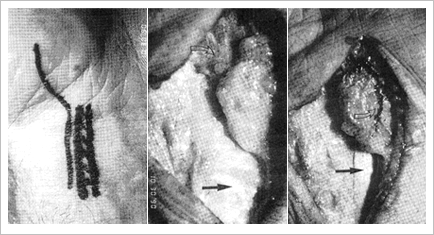

1st Dorsal Compartment Release

FCR Release